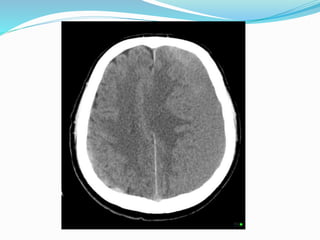

 CT scan is initial investigation of choice

 After 2 weeks it will appear as isodense

 After 3 weeks it will assume a lenticular shape &

hypodense in relation to brain

Diagnostic evaluation  CTscan is initial investigation of choice  After 2 weeks it will appear as isodense  After 3 weeks it will assume a lenticular shape & hypodense in relation to brain  In case acute on chronic SDH ,it may appear as mixture of hypodense & hyperdense material  Sometimes its difficult to distinguish between brain parenchyma & chronic SDH ,in this case contrast material 300 ml of 30 % diatrizoate meglumine is used which cause membranes of isodense hematoma to opacify.